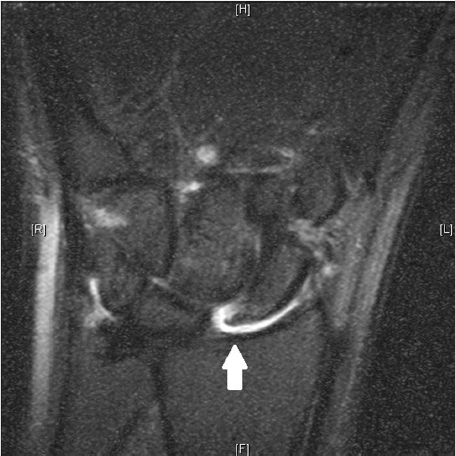

There are many radiographic indicators, including diastasis between the scaphoid and lunate on the PA radiograph greater than 3 mm (► Fig. 66.2a). Moreover, a clenched fist/pencil grip view (► Fig. 66.2b) drives open the SL interval and can accentuate the deformity. A cortical ring sign (► Fig. 66.2c) and an increased scapholunate angle (► Fig. 66.2d) are other indicators of this pathology. MRI studies are often performed (► Fig. 66.3), but have variable rates of sensitivity and specificity. 3 The gold standard for diagnosis of a SL ligament rupture remains diagnostic arthroscopy. The Geissler classification is used to characterize a tear. 4